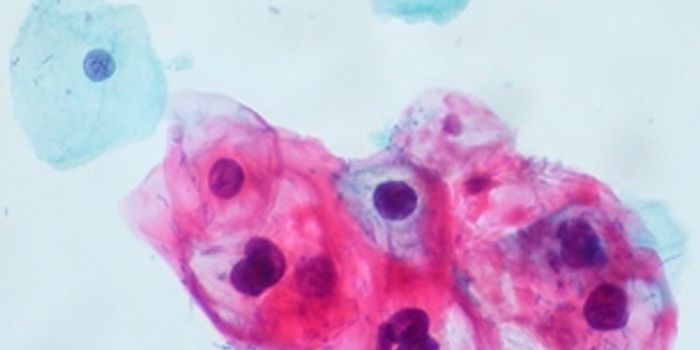

NOV 02, 2017Health & MedicineThe human papillomavirus (HPV) is known for its connection to cervical cancer. The exact mechanism isn't entirely cl ...